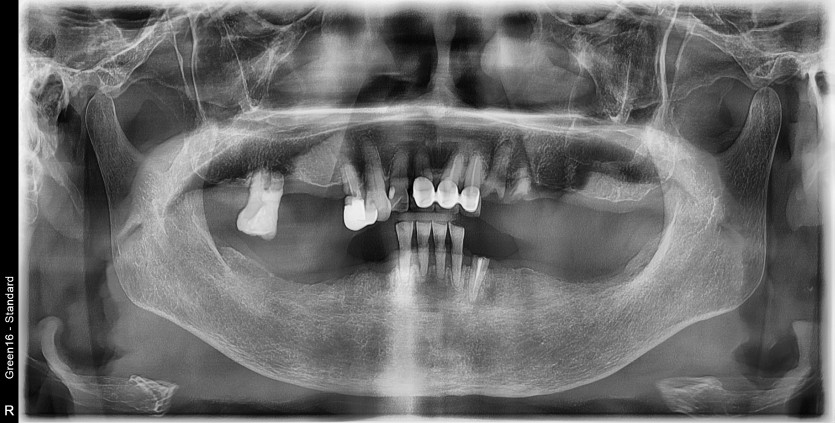

만 82세 하악 풀아치, 상악 임플란트(일부) 증례

하악 풀아치 증례입니다. (상악 구치부 임플란트 포함)

12개의 임플란트로 완성하였습니다.